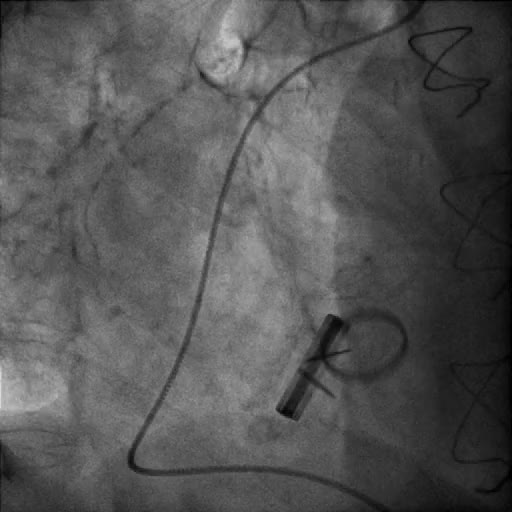

Catetere stimolatore nel ventricolo sinistro

Autore:

Chiara Bencini